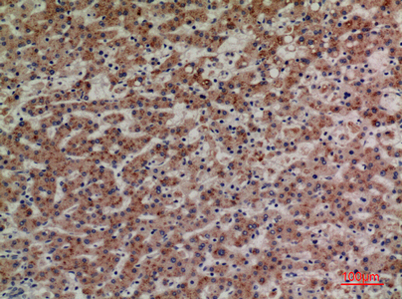

Product name: CD85g rabbit pAb

Dilutions: Western Blot: 1/500 - 1/2000. IHC-p: 1:100-300 ELISA: 1/20000. Not yet tested in other applications.

Immunogen: The antiserum was produced against synthesized peptide derived from the Internal region of human LILRA4. AA range:391-440